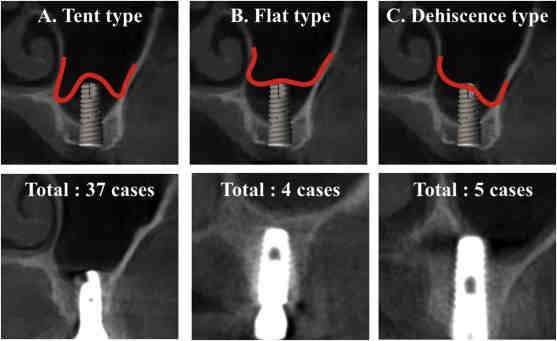

How long does it take for dental implants to fuse to bone?

Once the poles are set in the jaw bone, you should wait for the implant to fuse with the bone. This may interest you : What happens to my dental implants after i die. This process is known as osteointegration and usually takes about 4 to 6 months.

The first phase of the dental implant process is the burial of the implant in the jaw bone through a surgical procedure. The dental implant replaces the root of the tooth and needs time to heal. During this healing time, osseointegration (integration of the bone with the implant itself) occurs.